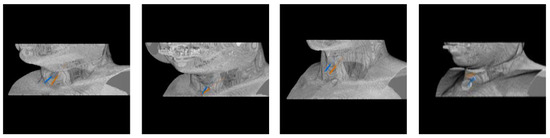

Automatic Needle Route Proposal in Preoperative Neck CT for Injection Laryngoplasty

- We propose the first automatic method to compute the optimal needle route in neck CT for TIL based on critical structure segmentation and minimal cost route search.

2. Methodology

2.4. Optimal Needle Route Search

3. Experimental Results

3.4. Needle Route Accuracy